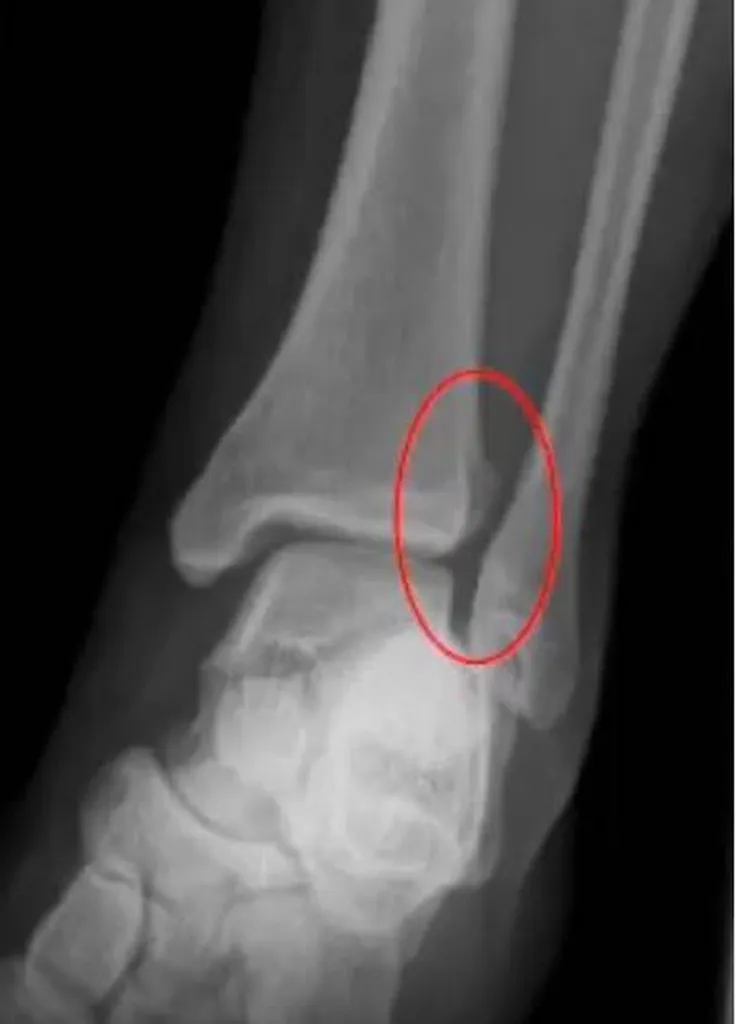

Les traumatismes en rotation sont particulièrement dangereux car la chaussure de ski ne limite pas ce mouvement. Les ligaments entre le tibia et le péroné sont susceptibles d'être rompus, entraînant des douleurs importantes.

Les radiographies initiales peuvent sembler normales, ce qui rend crucial de consulter un chirurgien spécialisé dans la cheville et le pied pour des examens plus approfondis, tels que l'IRM et des radiographies en charge, pour détecter ces blessures ligamentaires.